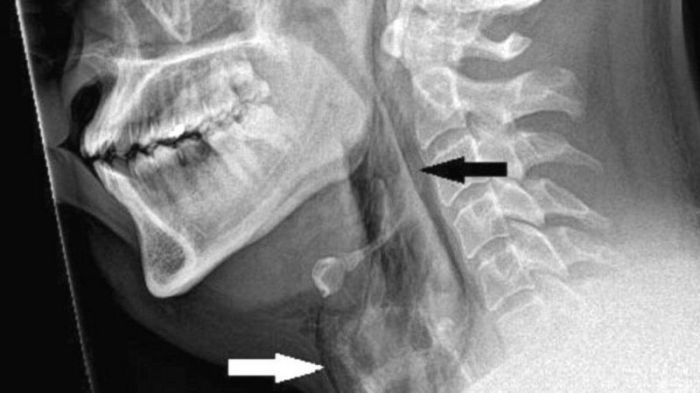

Os exames revelaram que ele sofreu uma ruptura de 2 mm na traqueia.

Quando os médicos examinaram o paciente, ouviram um estalo ao tocar seu pescoço e descobriram que ele não tinha controle dos movimentos.